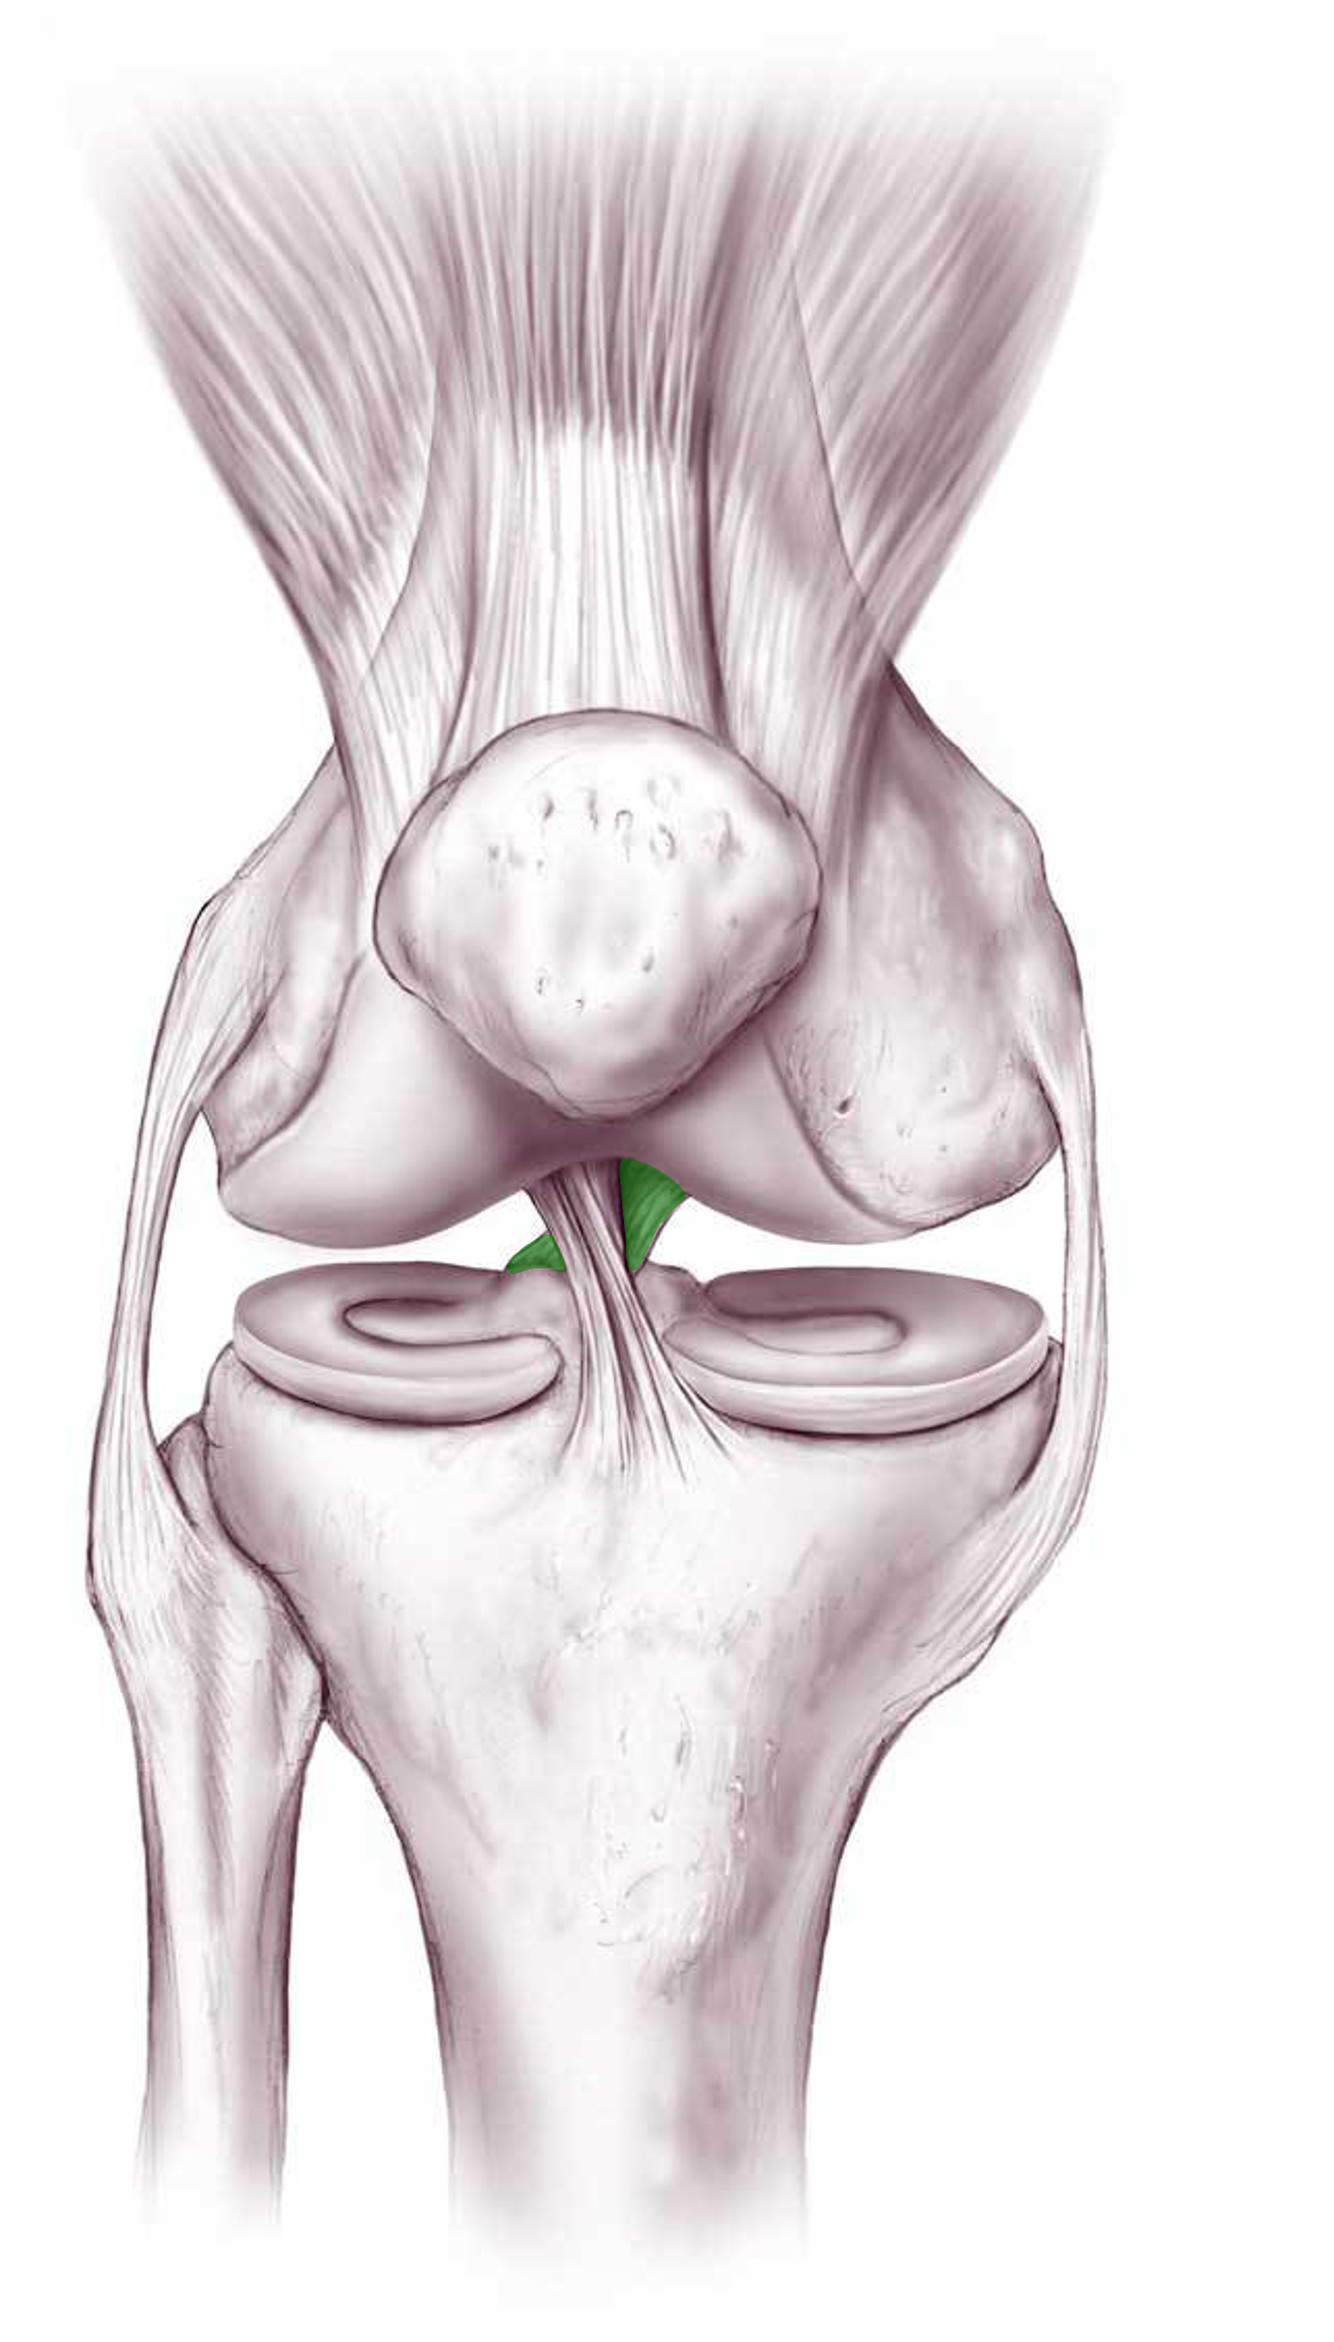

What is this structure?

Anterior cruciate ligament of the knee

What is this structure?

Posterior cruciate ligament of the knee

What is the function of this structure?

Anterior cruciate ligament of the knee

Stops anterior dislocation of knee

What is the function of this structure?

Posterior cruciate ligament of the knee

Prevents femur from sliding posteriorly on tibia